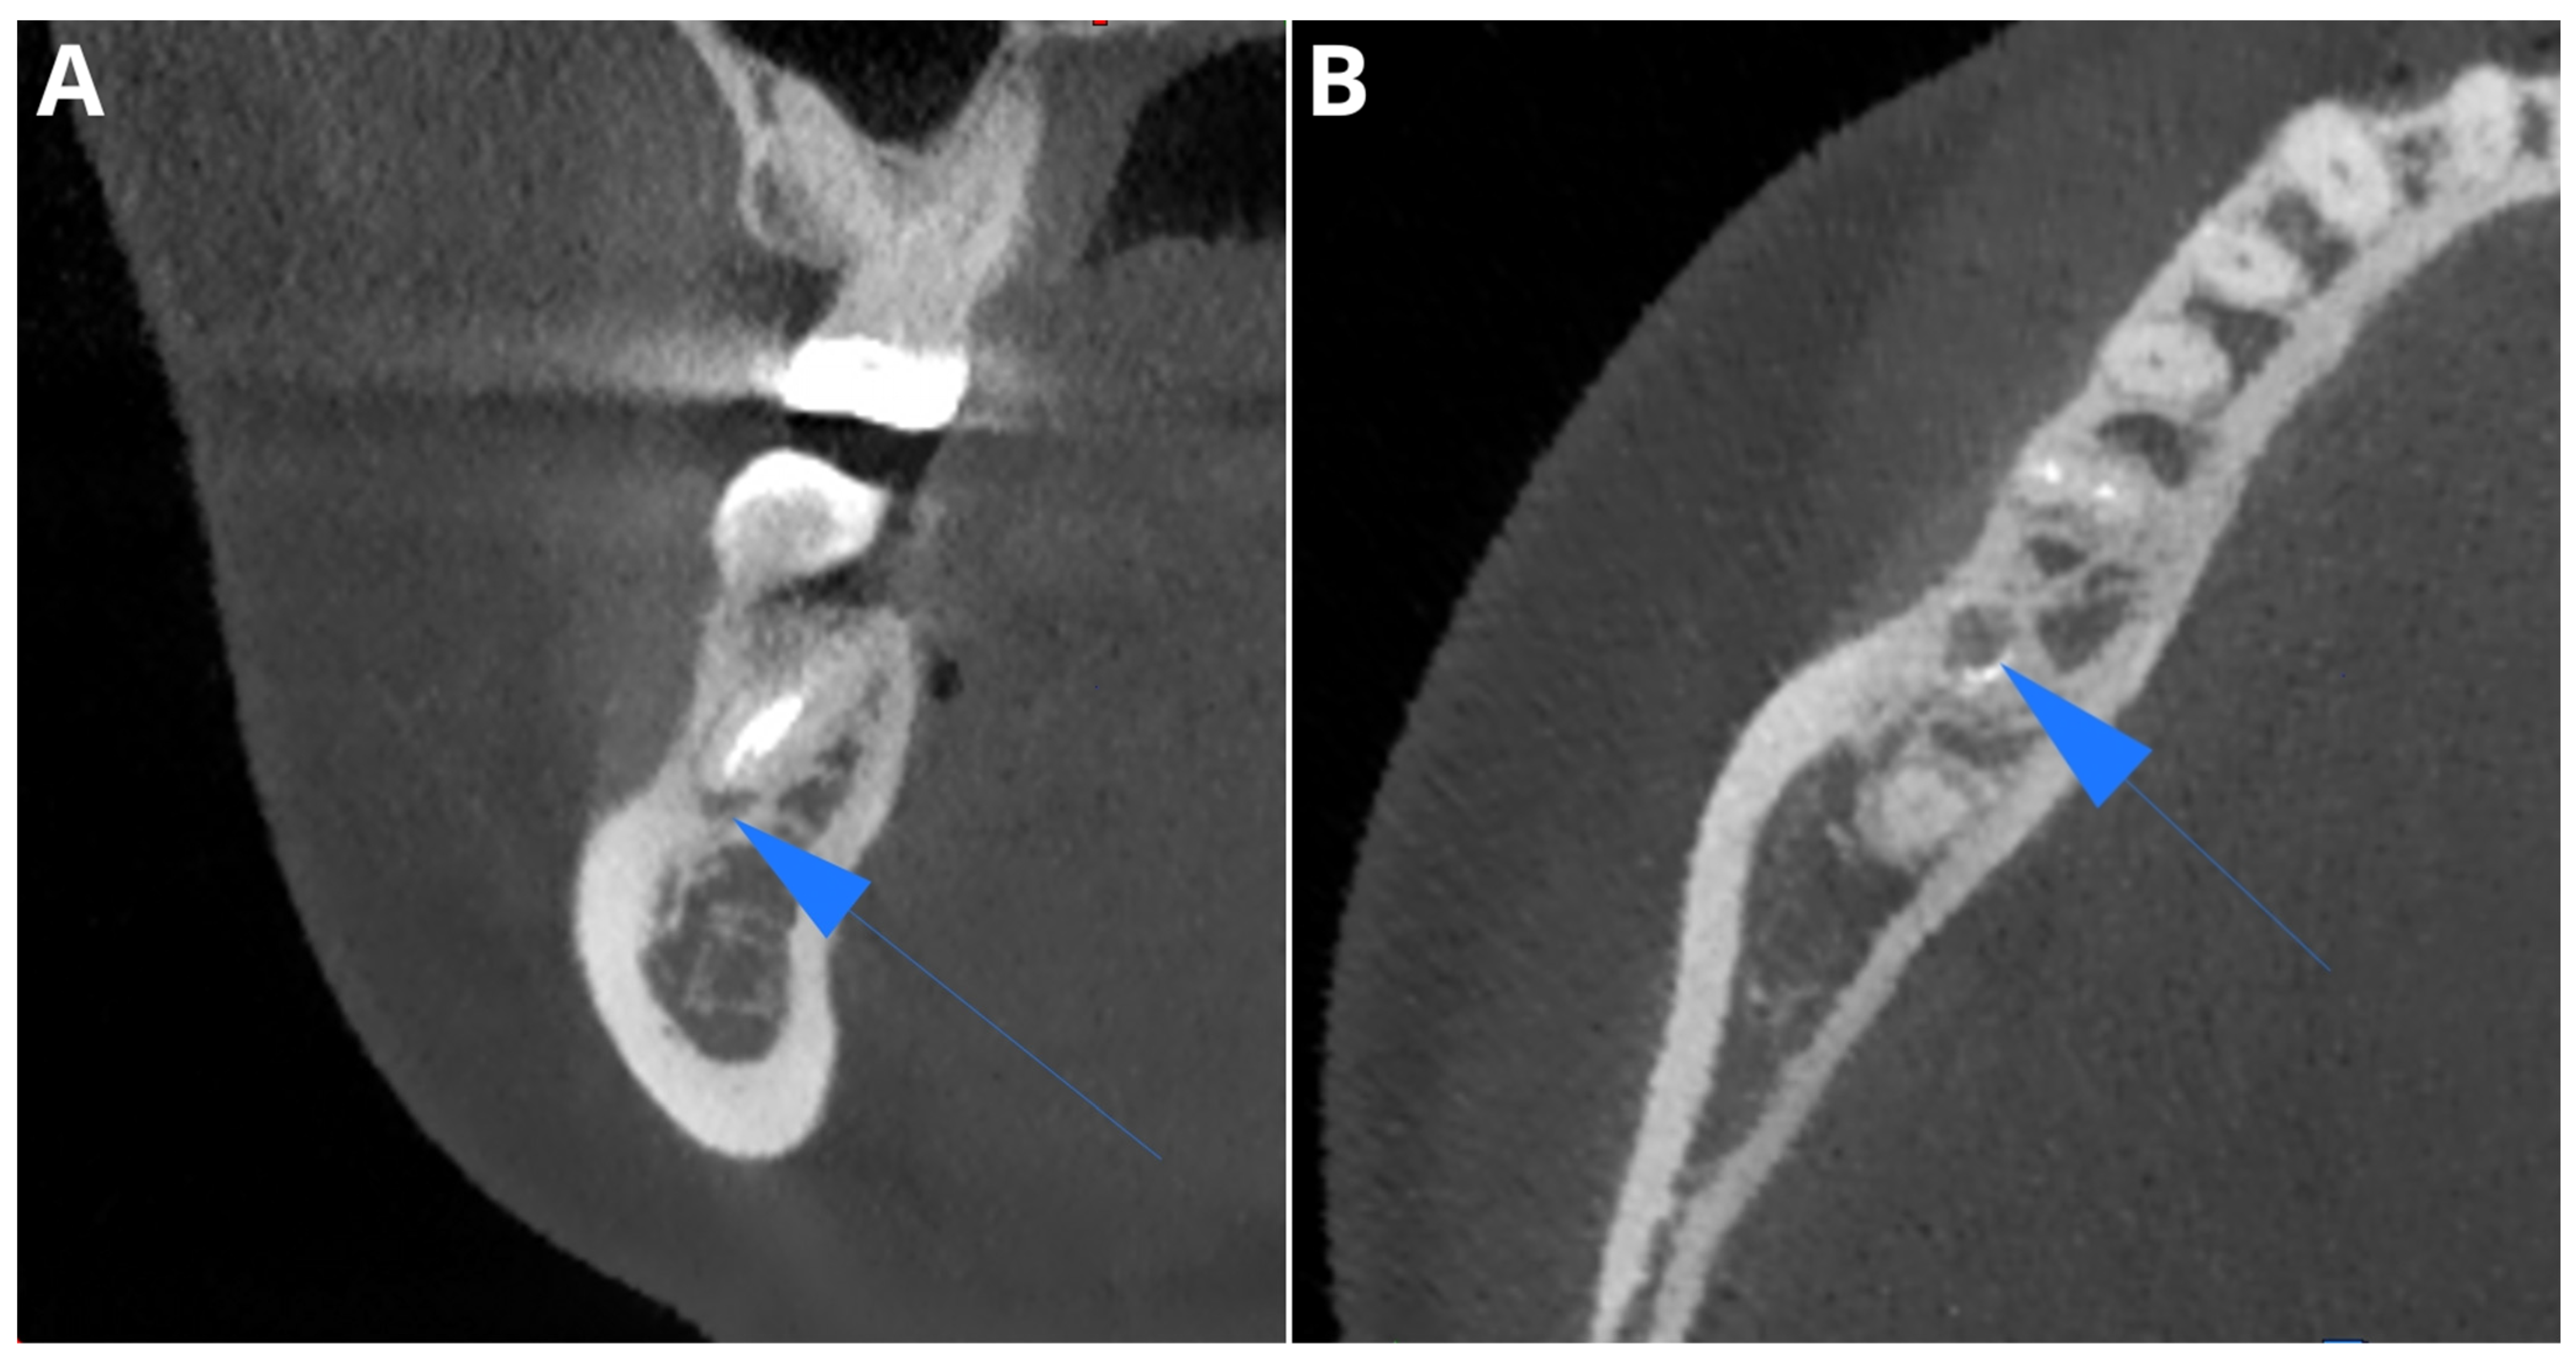

Periapical Lesions in Panoramic Radiography and CBCT Imaging—Assessment of AI’s Diagnostic Accuracy

2. Materials and Methods

2.2. Image Acquisition and Post-Processing